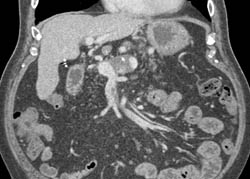

Partial Thrombosis of the Splenic Vein